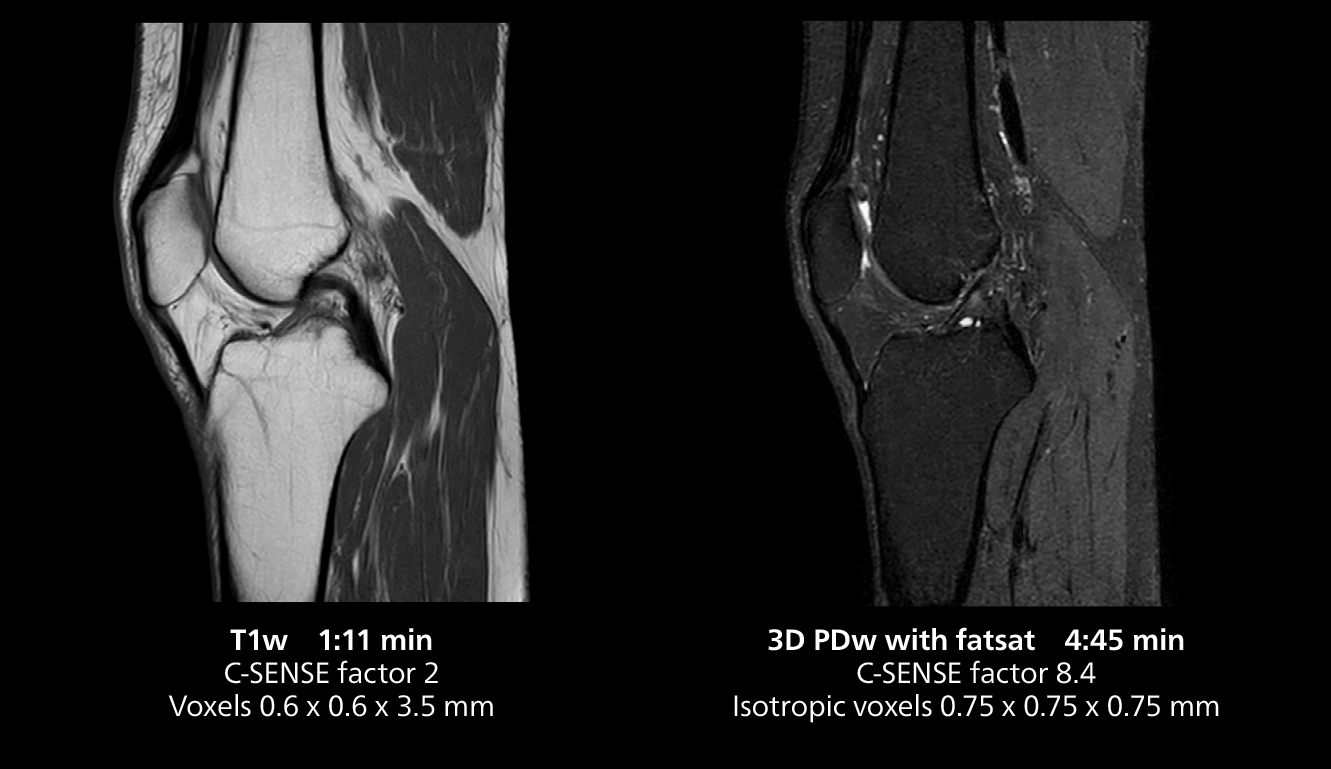

The isotropic high resolution 3D sequence in this MRI case allows for reformatting to obtain other orientations with high quality. Acquired on the MR 5300 system.

“We have more speed in 3D sequences,” Dr. Gellée states. “With Compressed SENSE, we can replace two or three 2D scans withone high-quality 3D scan. High quality additional orientations are then obtained by post-processing of the 3D data set, thus saving scanning time.”

According to Dr. Gellée, the hospital conducts an average of four studies each hour, totaling about 40-45 patients per day on their MR 5300. Studies are read by approximately 50 radiologists in the Bordeaux area. Dr. Gellée is especially satisfied with the image quality of the MR system. "I obtain higher image contrast and more anatomical precision than I was used to,” she says. “When I am able to choose, I request that studies be done on this system, because I get better anatomical image quality. For example, in the knees, I can get great images of the meniscus. To me, it looks as pretty as 3T.”